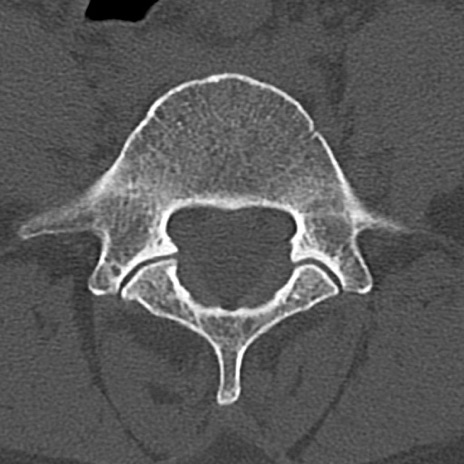

腰椎CT

横断像と矢状断像